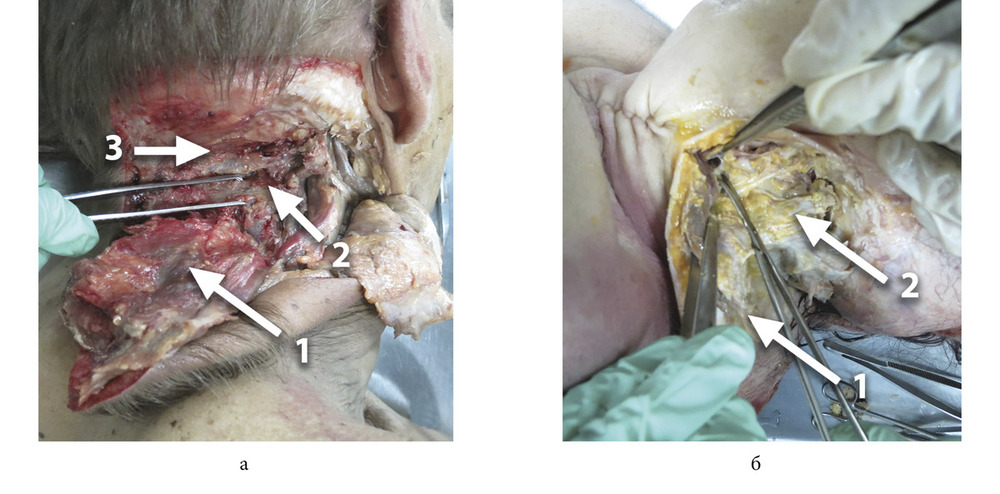

Результаты клинико-экспериментальной части исследования и эффективность разработанного оперативного доступа подтверждены следующим клиническим примером. В положении пациента лежа на боку либо вполоборота выполняли разметку и подготовку тканей к рассечению. Разрез кожи с последующим тактичным и деликатным рассечением подкожно-жировой клетчатки, мышц, фасций шеи проводили в двух направлениях, что в последующем способствовало мобилизации трех продольных мышечных трактов.

Вертикальный разрез кожи с подкожно-жировой клетчаткой начинали в проекции наружного затылочного выступа и продлевали книзу по линии остистых отростков до уровня IV—V шейных позвонков. Из этой же точки выполняли разрез в горизонтальном направлении, который продлевали в виде полусферы параллельно проекции поперечного синуса по верхней выйной линии в направлении к тыльной поверхности ушной раковины и далее к переднему краю грудино-ключично-сосцевидной мышцы к ее нижней части. На границе верхней и средней трети данного разреза при необходимости выполняли дополнительный, окаймляющий мочку уха разрез, который продлевали кверху по предушной складке (см. рисунок).

Высокая жизнеспособность кожно-подкожного лоскута обусловлена формированием широкого основания (1:2) с сохранением анатомической целостности сосудистых и нервных структур за счет тактично-деликатного разъединения фасциальных и мышечных футляров. Мобилизация поверхностного лоскута, выкроенного в пределах указанных выше границ, позволяет продолжить тактичную диссекцию сухожилий грудиноключично-сосцевидной, трапециевидной, ременной и других мышц с отделением от основания черепа и позвонков в едином фасциальном футляре. Тактично-деликатную диссекцию выполняют с соблюдением основного принципа, базирующегося на сохранении целостности поперечного сечения мышц. Дальнейшее послойное разобщение осуществляют в вертикальной плоскости с сохранением целостности фасций сосудистых перфорантов, имеющих вертикальное направление. Формирование полнослойного лоскута по предложенной методике обеспечивает его свободное смещение во всех направлениях, в том числе в сторону ипсилатерального плеча, что позволяет визуализировать патологический процесс любой локализации. Кроме того, мобильность препарированных тканей обеспечивает объективную визуализацию костных структур от затылочного выступа до поперечных отростков позвонков в нижнем шейном отделе. Дальнейшая диссекция широким доступом дает возможность визуализировать внутрипозвоночные анатомические структуры, патологические образования любого размера с последующим их удалением и одномоментной реконструкцией, используя методы пластического замещения дефектов местными тканями.